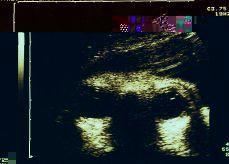

Un ecógrafo Toshiba SSA-250A para la observación constante de los movimientos oculares del feto, señalados sobre el registro cardiotocográfico con un señalizador de eventos. Los movimientos del cuello, cabeza y miembros superiores detectados simultáneamente se señalaron asimismo en el registro en el canal correspondiente a la dinámica uterina con el fin de complementar la información proporcionada por el actógrafo (Figs. 1 y 2).

Figura 1. Observación ecográfica de la actividad ocular fetal como variable caracterizadora de los estados de comportamiento fetal.